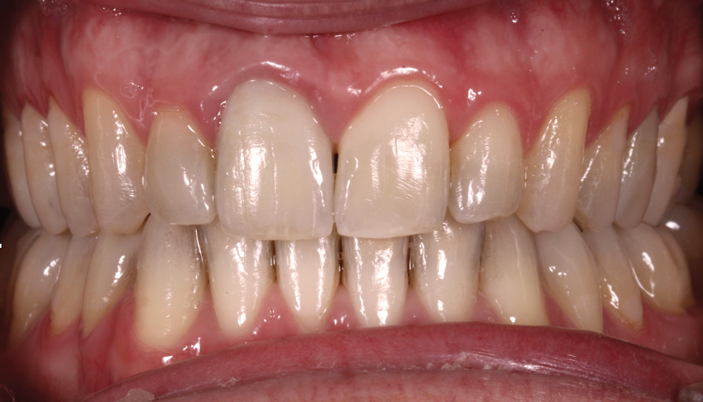

Fig 8. A class III adult male patient required surgical orthodontic treatment. The patient had anterior and posterior crossbites and required leveling of a deep curve of Spee during presurgical orthodontics.

Figure 8

Fig 9. A class III adult male patient required surgical orthodontic treatment. The patient had anterior and posterior crossbites and required leveling of a deep curve of Spee during presurgical orthodontics.

Figure 9

Fig 10. A class III adult male patient required surgical orthodontic treatment. The patient had anterior and posterior crossbites and required leveling of a deep curve of Spee during presurgical orthodontics.

Figure 10